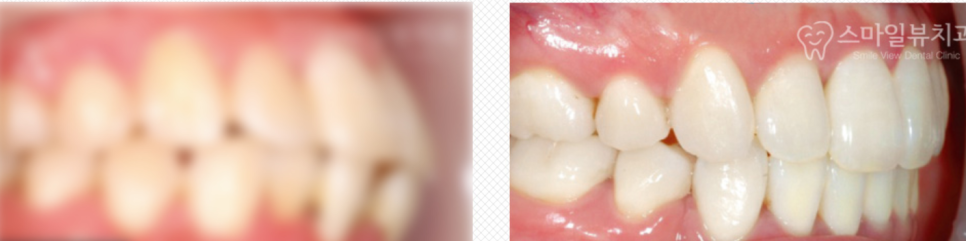

머지 않아 바로 위의 사진처럼 중년 돌출입을 가지셨던 분께서도 아주 예뻐지실 거예요.

지금도 많이 들어가서 아주 만족하게 진행하고 계시답니다.

나중에 중년여성분 돌출입교정이 완전히 끝나면 다시한번 올려드리도록 하겠습니다.